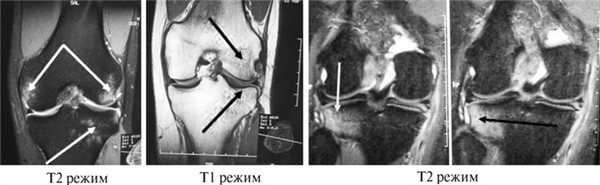

При МРТ-исследовании у 86 пациентов с острой травмой коленного сустава мы обнаружили в 39 (43%) случаях не только мягкотканные повреждения связочного аппарата, менисков, хряща, но и участки с контузией губчатой части мыщелков бедра и большеберцовой кости разной степени выраженности. Без применения МРТ такие травматические изменения (контузия) губчатой кости ранее вообще не диагностировались никакими другими методами. Мы обратили внимание на то, что все эти пациенты в отличие от остальных пациентов с острой травмой коленного сустава жаловались на выраженный болевой синдром и имели длительный период сгибательно-разгибательной контрактуры коленного сустава. В таких случаях мы откладывали оперативное лечение до стихания острого периода и болевых ощущений (рис. 3).

Рис. 3. МРТ-изображение коленного сустава в Т1- и Т2-режимах с участками острых контузионных изменений в мыщелках бедренной кости и наружном мыщелке большеберцовой кости (указано стрелками).

С помощью МРТ-контроля мы обнаружили, что внутрикостные кровоизлияния в мыщелках бедра и большеберцовой кости регрессировали примерно через 2—4 мес после травмы при условии целенаправленного медикаментозного и физиотерапевтического лечения именно этих контузионных явлений. По мере того как, по данным МРТ, костная ткань становилась нормальной, уменьшались болевой синдром и болевая защитная контрактура коленного сустава, возникала более благоприятная ситуация для дальнейшего оперативного лечения. И только на этом этапе всем 39 пациентам была проведена реконструкция ПКС из аутотканей по стандартным артроскопическим методикам.